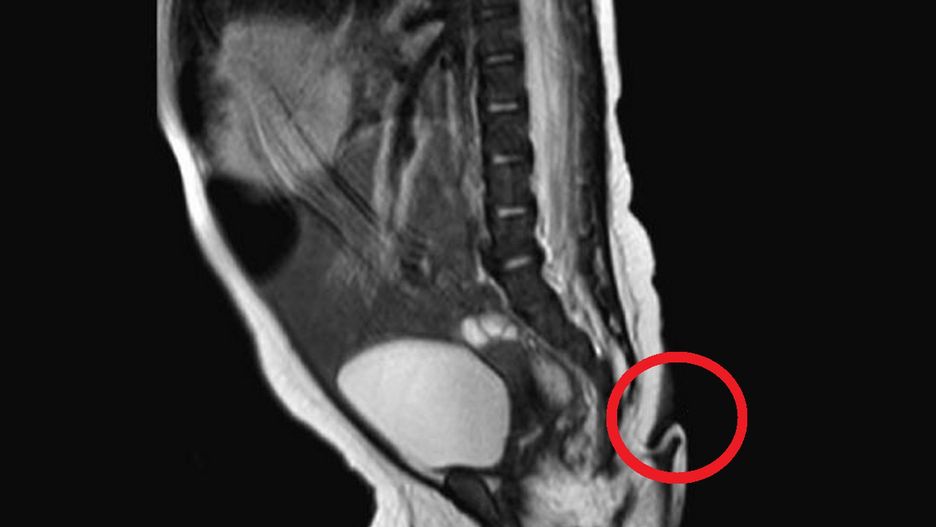

Zaraz po tym, jak lekarze odebrali poród, zauważyli kilkucentymetrowy ogon, który wyrastał w okolicy kości ogonowej, nad pośladkiem dziecka. Zgodnie z raportem czasopisma "Jorunal of Pediatric Surgery Case Reports" ogon miał około 6 cm długości, był miękki, pokryty skórą i cienkimi włosami. Co więcej, ogonem można było swobodnie poruszać, a podczas poruszania nim, noworodek nie odczuwał żadnego bólu.

Do tej pory na całym świecie odnotowano mniej niż 200 przypadków dzieci urodzonych z ogonem. Dr Josue Rueda, jeden z lekarzy, który zajął się dziewczynką po urodzeniu, wyznał, że jest to pierwszy taki przypadek w Meksyku. Co ciekawe, nic nie wskazywało na to, że dziecko urodzi się z ogonem. Lekarze zapewniali, że ciąża kobiety przebiegała prawidłowo, a co więcej, przyszła mama nie była narażona na żadne czynniki, które mogłyby wpłynąć na "rozwój ogona".

Dwa miesiące po narodzinach dziewczynki i jednocześnie po przeprowadzeniu niezbędnych badań, lekarze z Meksyku zdecydowali się na chirurgiczne usunięcia ogona. Odcięta narośl została wówczas poddana analizie. Badania pokazały, że był to ogon, który przypominał ogony występujące u zwierząt.

Dziewczynka urodziła się z 6-centymetrowym ogonem.

Dziewczynka urodziła się z 6-centymetrowym ogonem. © sciencedirect.com

Struktura narośli składała się bowiem z mięśni, naczyń krwionośnych oraz nerwów. Eksperci tłumaczą, że jeżeli płód rozwija się prawidłowo, taka narośl zostaje wchłonięta przez resztę ciała. Naukowcy do tej pory nie wiedzą jednak, dlaczego w niektórych przypadkach ogon nie ulega wchłonięciu.